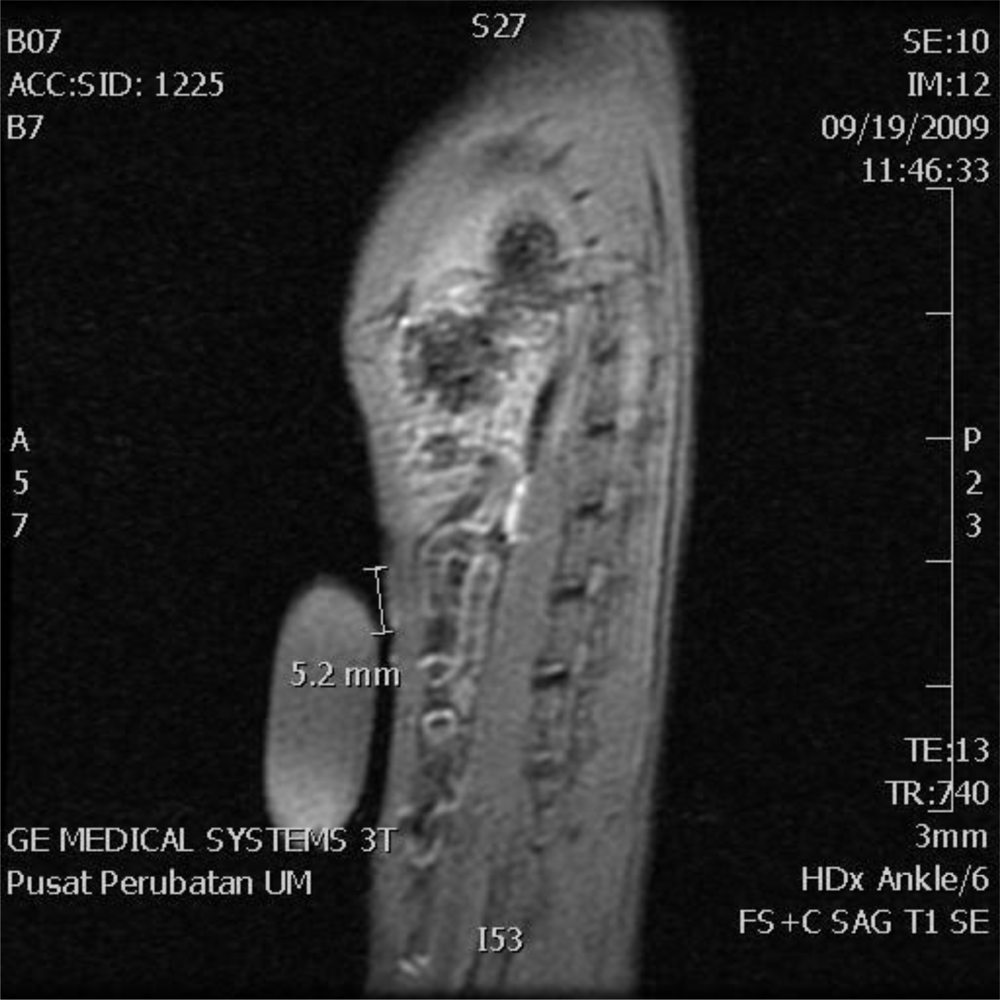

Sagittal T1 Fat Sat contrast enhanced image of the rat was successfully scanned using gadolinium as a contrast agent at 14 weeks after injection of NMU (Figure 2). There was marked enhancement of the upper set of the mammary glands in the post gadolinium images measuring 2 mm in the long axis but no noticeable enhancement in the lower mammary glands.

Figure 2.

Sagittal T1 Fat Sat magnetic resonance imaging (MRI) contrast image of a rat at 14 weeks after injection of a cancerous agent. There was marked enhancement of the upper set of mammary glands: 5.2 mm in length in this rat (between small arrows) but no enhancement of the lower set of mammary glands.

Despite the lack of physical evidences, marked enhancement of tumor in the mammary gland of rats treated with NMU was successfully detected by contrast enhanced MRI. Most previous imaging studies of the mouse model focused on large mammary tumors and were performed in dedicated animal MRI units of 4.7 Tesla to 7 Tesla. This study showed the possibility of detecting very small amounts of breast cancer tissues using standard clinical 3 Tesla MRI equipment. In addition, the study was performed with just a basic custom made mold to house the rat, a pre-estimated dosage of contrast according to the weight of the rat and imaging within a standard knee coil. However, more cases that correlate to the biopsies need to be performed.

When taken together, the data of our study demonstrated the possibility of contrast enhanced MRI recognition of a tumor at an early stage of breast cancer when the APRP changes in the rat sera were not able to illustrate clear differences.

Contrast enhanced MRI using gadolinium as the contrast agent appeared to have the capability to detect the NMU-induced tumor at 14 weeks of development. However, the serum APRP profiles of rats before and 18 weeks subsequent to NMU injections did not show any significant difference, although pathological examination of the breast tissues of the animals demonstrated obvious evidence of early tumor development.